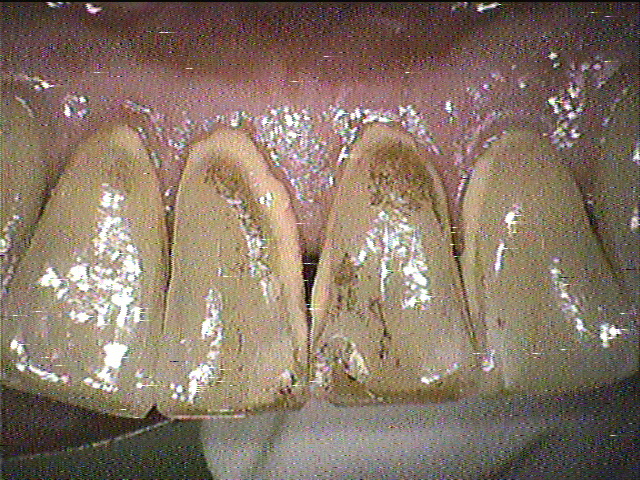

クリーニング前

下の前歯と上の前歯の裏側の写真です。

ステインがとてもつきやすく、3ヵ月毎にクリーニングにいらしています。

この患者さんはコーヒーと赤ワインをよく飲まれているそうなのですが、

この2つはステインが特につきやすい飲み物です。